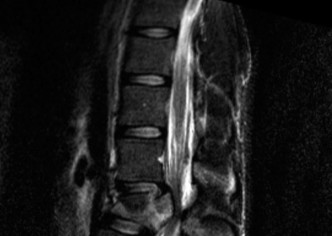

Prognosis of central cord syndrome? Indications for surgery for this disorder? CASE 2 A 56-year-old man presents to you with a chief complaint of severe right buttock, posterior thigh, and lower leg pain for 12 weeks. It radiates to the lateral aspect of his foot, and it is worse with sitting or standing for prolonged periods and with walking. Now over the past 2 weeks, he reports difficulty with toe push-off on the right side. Treatment so far has been nonsteroidal anti-inflammatory drugs (NSAID), physical therapy, and an epidural injection without significant relief. Physical examination findings include 4/5 right ankle plantar flexion, a positive straight leg raise on the right, and an absent right Achilles tendon reflex. Images of his lumbar spine are shown in Figures 1–4 and 1–5.

Figure 1–5

The correct answer is (C). The patient presents with classic right S1 radiculopathy and new onset plantar flexion weakness. The images demonstrate a right-sided paracentral disc herniation at L5/S1 compressing the traversing S1 nerve root. Despite nonoperative management, he continues to have severe pain and new weakness. Continued physical therapy or an epidural injection is unlikely to improve the patient’s pain at this time. In the setting of neurological decline, surgery is more strongly indicated. Lumbar discectomy is the most appropriate procedure for this patient. Fusion would only be indicated if there were radiographic signs of instability, which are not present.